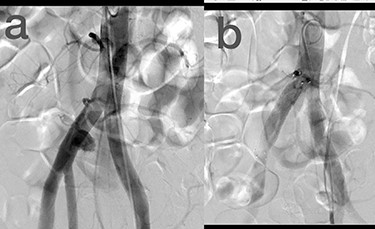

Sites of injury included 6 Posterior Tibialis arteries (27.2%) (Fig. 1), 2 deep femoral arteries (9.09%), 2 Superficial femoral arteries (9.09%) and 2 maxillary arteries (9.09%). We had only one injured artery (4.54%) in each of the following sites: internal pudendal a., Axillary a. (Fig. 2), Proneal a., Lumbar a., External carotid a., Anterior Tibialis a., common iliac a. (Fig. 3), temporal a., Thoracic aorta and Internal iliac artery (Fig. 4).

(a) Internal iliac artery before intervention, (b and c) after coil embolization.